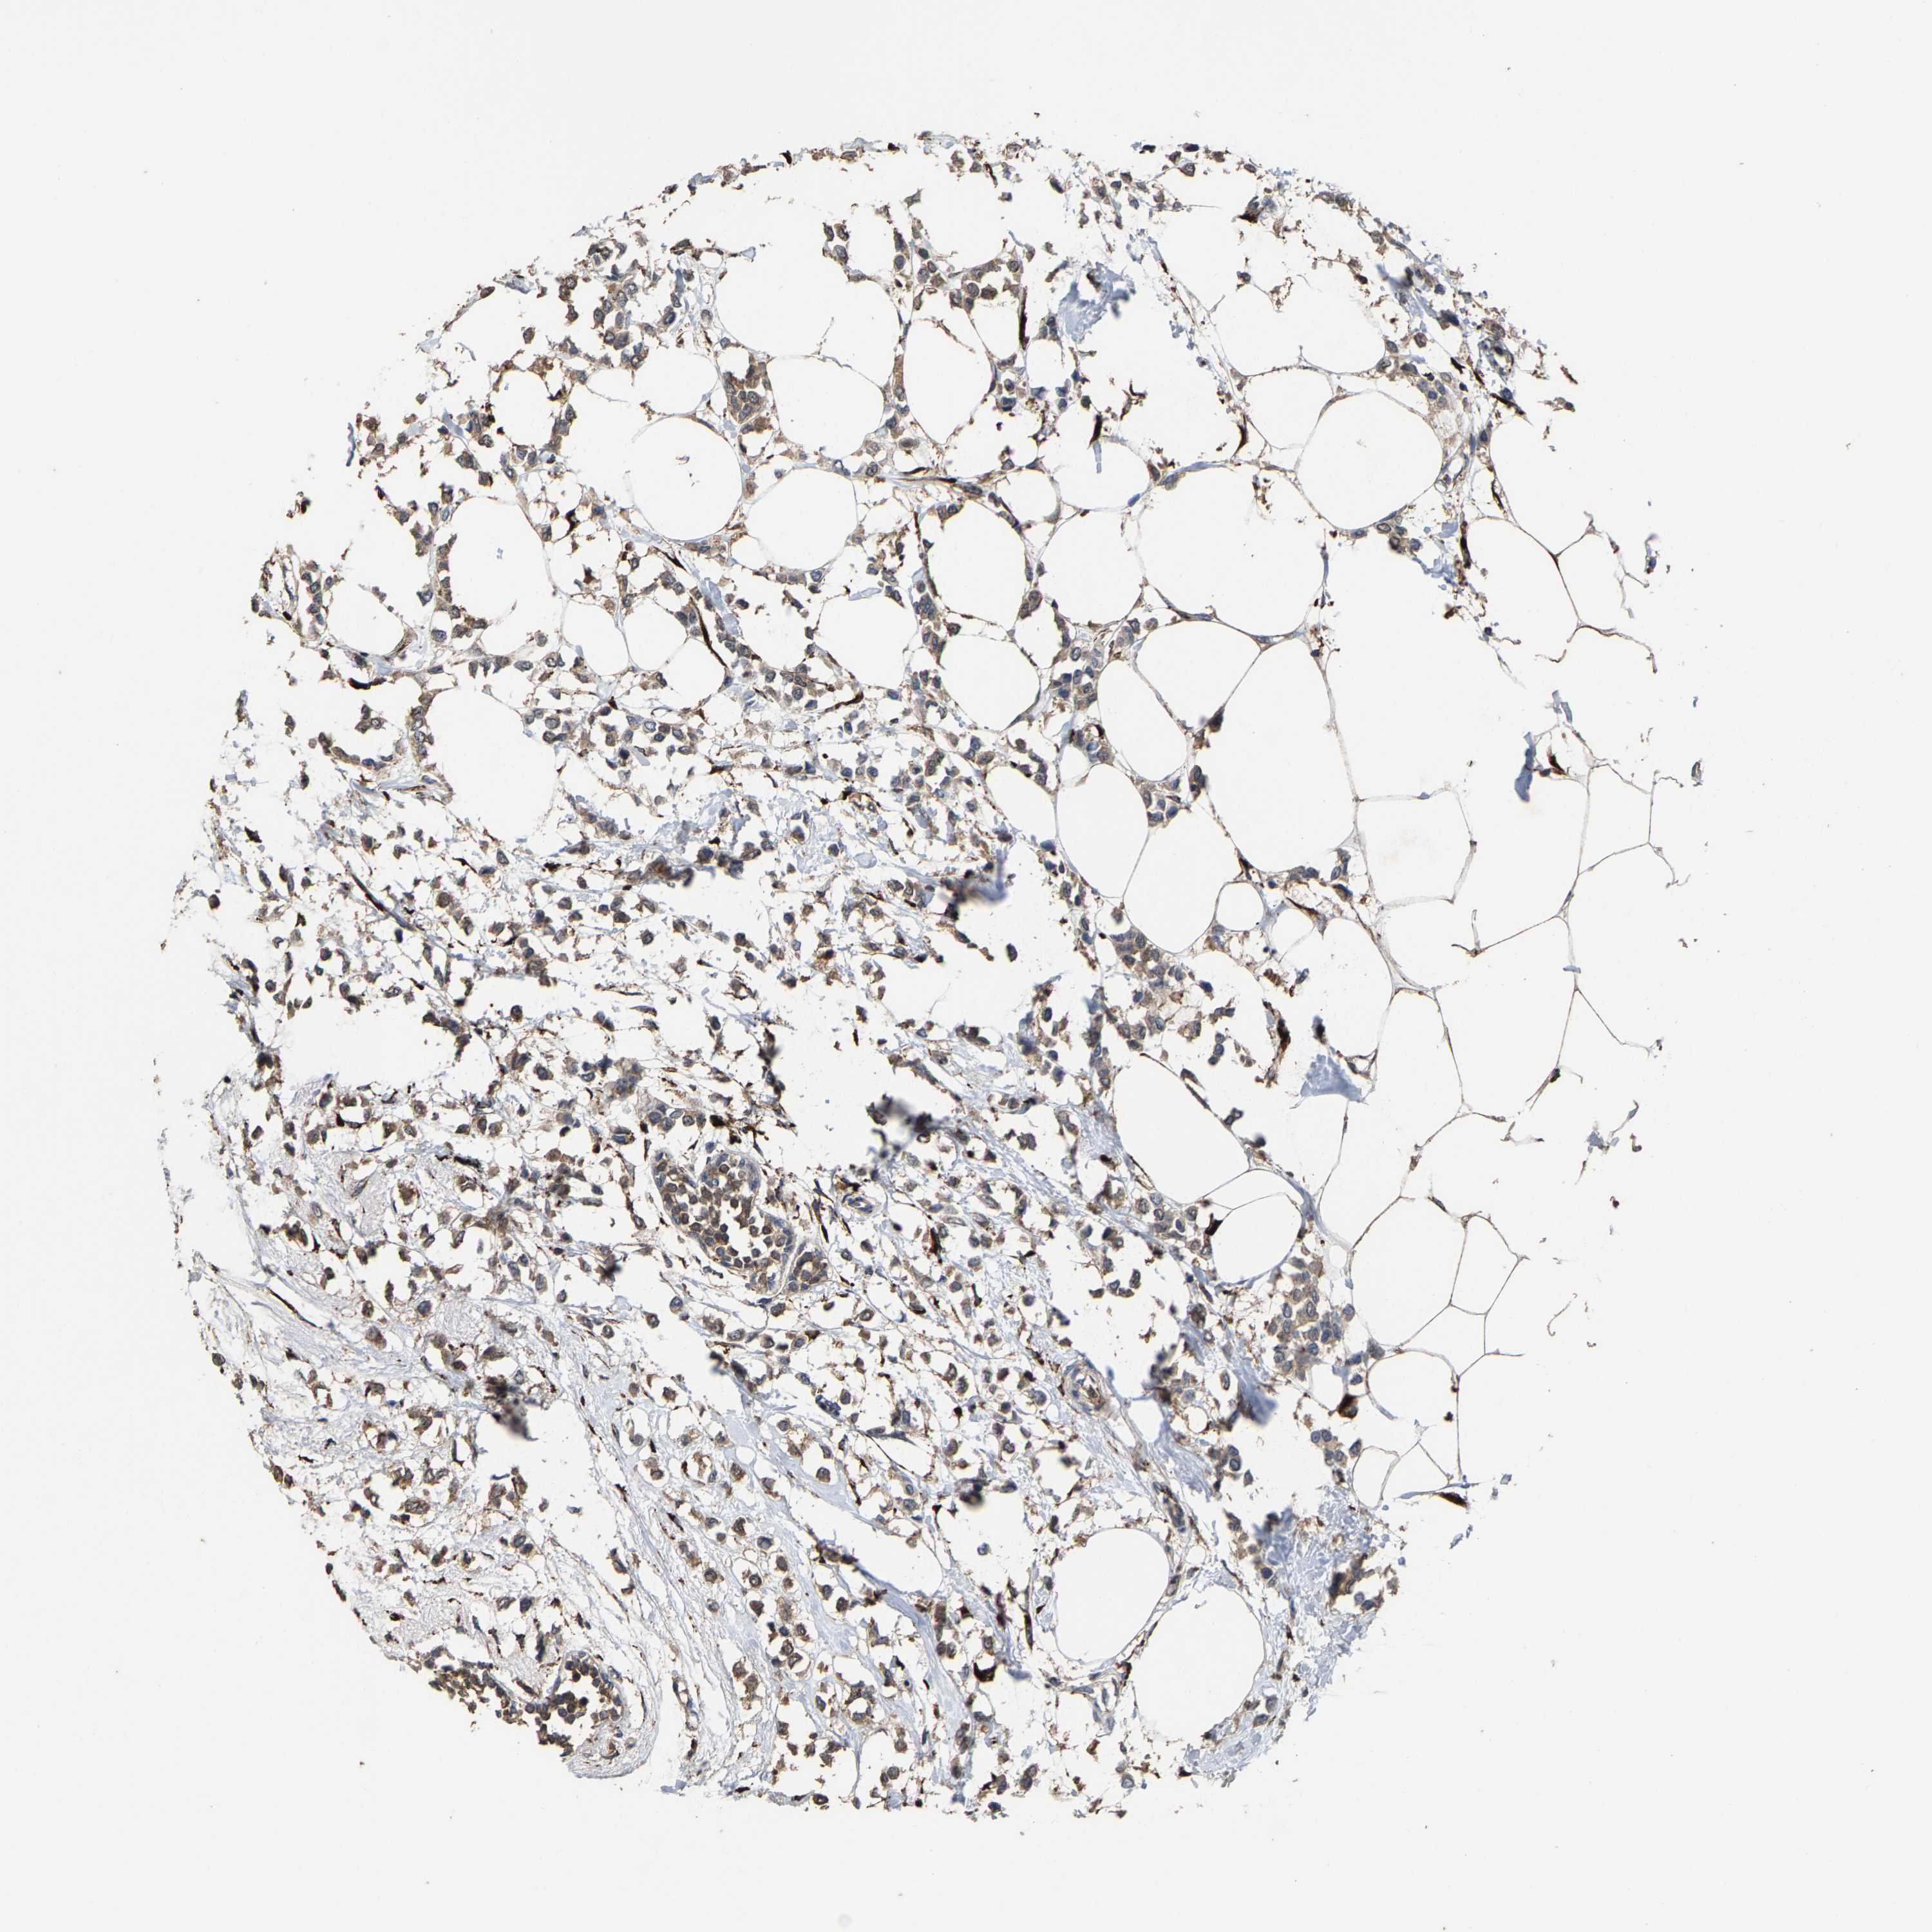

CANCER BREAST CANCER Show tissue menu

BRCA TCGA BRCA VALIDATION PROTEIN EXPRESSION